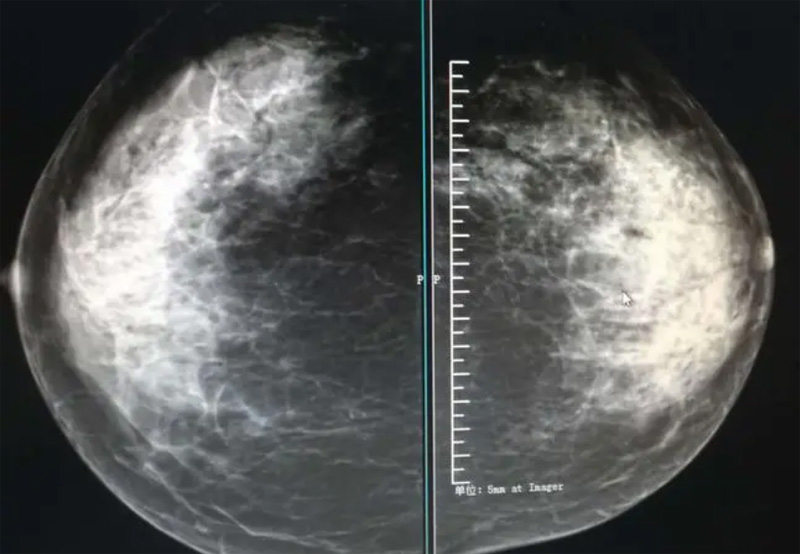

攝影診斷規范乳腺DR有頭尾位及內外側斜位診斷概念和診斷術語

乳腺DR的檢查中為了讓乳腺相關疾病的篩查需要更高質量的檢查圖像。檢查前期的準備工作非常重要。醫生跟病患的有效溝通。要跟檢查者說明檢查過程,特別是體位跟擠壓乳房帶來的不適應。放松心情,檢查過程中得到充分的合作。正確的擺正位置乳腺DR可以拍攝到更優質清洗高質量的X線圖像。乳腺DR檢查需要再月經后檢查,但是對病癥明顯的就不受這個限制。

乳腺DR攝影體位有頭尾位及內外側斜位,

乳房在片子的中央,乳頭切線位,可見小部分胸大肌,內側乳腺組織應全部包括在片中,外側乳腺組織盡可能包括在片中。一張好的MLO位圖像顯示如下:乳房被推向前上,乳腺實質充分展開,胸大肌可見,較松弛,下緣達到乳頭水平,乳頭在切線位,部分腹壁包括在片中,但與下部乳腺分開,絕大部分乳腺實質顯示在片中。乳腺組織外緣可見乳頭的輪廓;乳腺后方的脂肪組織被很好地顯示出來,乳房無皺褶。對于CC位及MLO位顯示不良或未包全的乳腺實質,可以根據病灶位置的不同選擇以下體位:外內側位(LM)、內外側位(ML)、內側頭尾軸位(MCC)、外側頭尾軸位(LCC),尾葉位(CLEO)及乳溝位。在臨床實踐中,對于常規體位上發現的異常改變,可以進一步采取一些特殊的攝影技術,包括局部加壓攝影、放大攝影或局部加壓放大攝影技術。

2、規范觀圖程序:屏幕軟閱讀或在專用日光觀片燈下膠片閱讀,后者應同時準備白熾強光燈及觀片放大鏡。注意雙側乳腺配對觀察,推薦雙眼橫向掃描,進行雙乳相同部位圖像比較分析。

3、乳腺實質背景的確定:觀察乳腺實質與脂肪的構成比例,了解乳腺實質類型,以判斷對某些乳腺攝影征象敏感性的影響,有利于確定乳腺攝影對疾病的診斷價值。

必須指出的是,美國放射學會提出的乳腺影像報告和數據系統(Breast Imaging Reporting and Data System, BI-RADS)將乳腺分為4型:脂肪型(乳腺內幾乎全部為脂肪組織,腺體組織占25%以下)、少量腺體型(乳腺內散在腺體組織,大約占25%~50%)、多量腺體型(乳腺呈不均勻致密表現,腺體組織大約占51%~75%)、致密型(乳腺組織非常致密,腺體組織占75%以上)。這種分型的主要意義在于說明X線對不同乳腺類型中病變檢出的敏感性不同,對發生在脂肪型乳腺中病變的檢出率很高,而對發生在致密型乳腺中病變的檢出率則有所降低,臨床醫師了解這一點很重要。